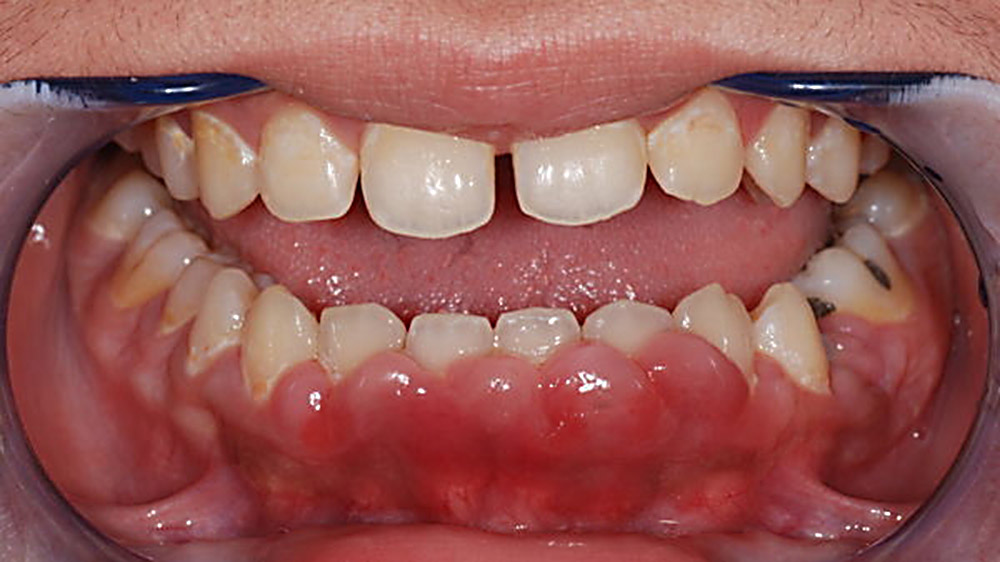

- Первая. Отмечается избыточный рост десневого края и межзубных сосочков. Утолщение, имеющее вид валика, может достигать 1/3 высоты зуба.

- Вторая. Разрастание десны прогрессирует и закрывает уже половину зуба. При приеме твердой пищи или гигиенических процедурах начинают появляться кровотечения.

- Третья. Десневой край и сосочки разрастаются до полного закрытия зубов. Десны могут перекрывать режущий край зубов и жевательную поверхность. Возникают грануляции (образование новой заживляющей ткани).

- увеличение массы десен, их набухание;

- уплотнение гипертрофированных тканей;

- заполнение межзубных промежутков тканями десен;

- покрытие значительной части зубов тканями десен;

- гомогенный розовый цвет тканей десен.